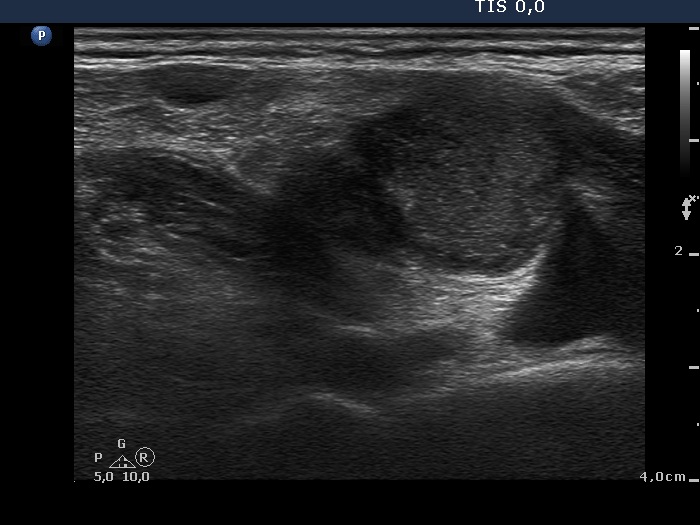

The mass in the left side of the neck corresponded to a conglomerate of multiple lymph nodes. These were irregular in shape and presented cystic and necrotic areas. There was no hilum present. The lymph nodes were avascular.